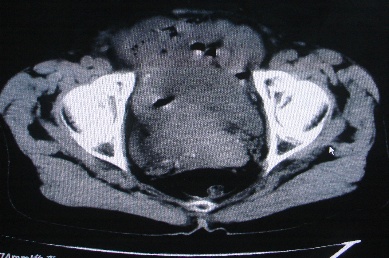

以下是引用卜一在2007-4-30 15:29:00的发言:[br]子宫明显增大,不规则,子宫壁不规则增厚,子宫腔明显缩小,子宫右侧软组织团块与子宫关系密切,内见低密度坏死区。考虑:子宫癌并周围侵润。